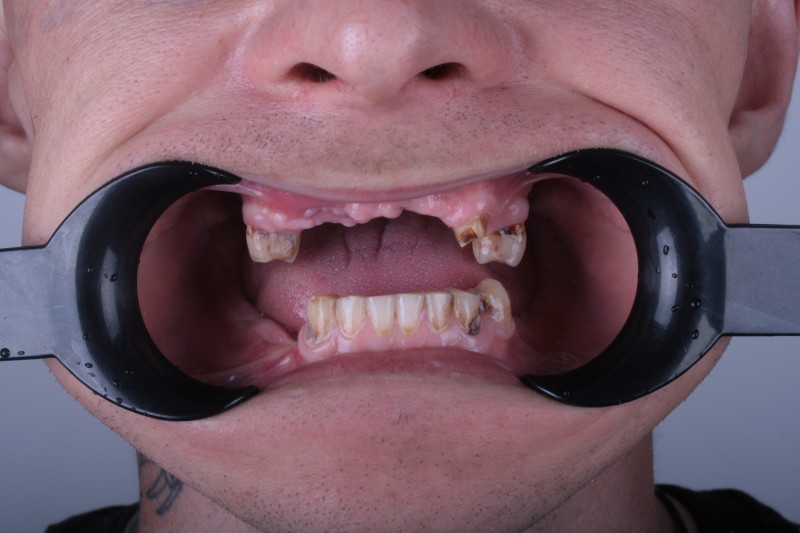

Фотографии до и после: Имплантация

На странице представлено портфолио стоматологий Самары с фото работ до и после имплантации зубов. Мы собрали разные клинические случаи: одиночные импланты, восстановление нескольких зубов и полная реконструкция зубного ряда. Здесь вы можете видеть, как выглядят восстановленные зубы, меняется форма улыбки после процедуры. Изучите результаты до и после имплантации зубов, чтобы оценить качество работы врачей и выбрать стоматологию в Самаре, которая поможет вернуть функциональность и эстетику вашей улыбке.

Имплантация

Имплантация All-on-4

Имплантация All-on-4

Имплантация All-on-4

Имплантация All-on-4

Имплантация All-on-4

Имплантация All-on-4

Имплантация All-on-4